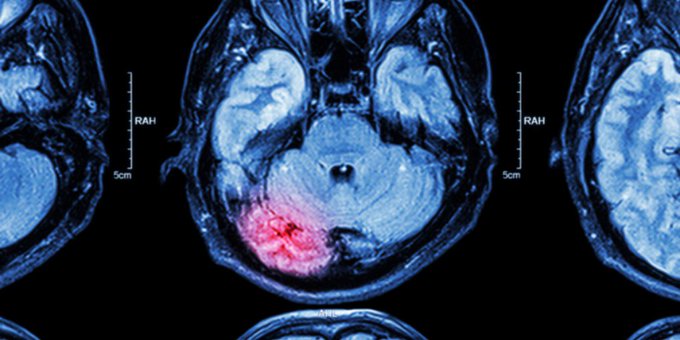

Un accidente cerebrovascular ocurre cuando se detiene el flujo sanguíneo hacia una parte del cerebro. ¿Cuáles son los factores de riesgo de los ataques cerebrales? Aquí lo que debes saber ow.ly/uaV750wWcIu #WorldStrokeDay